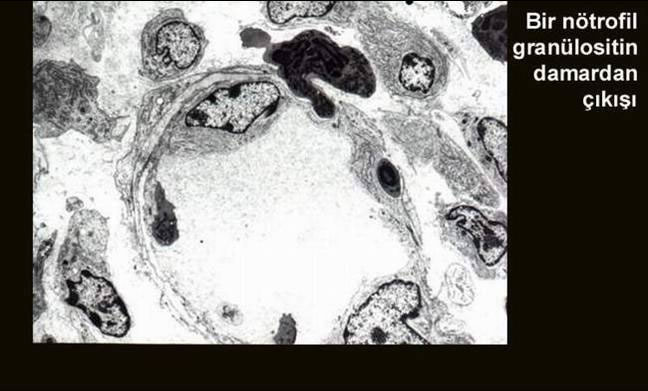

FD/kemotaksi.jpg